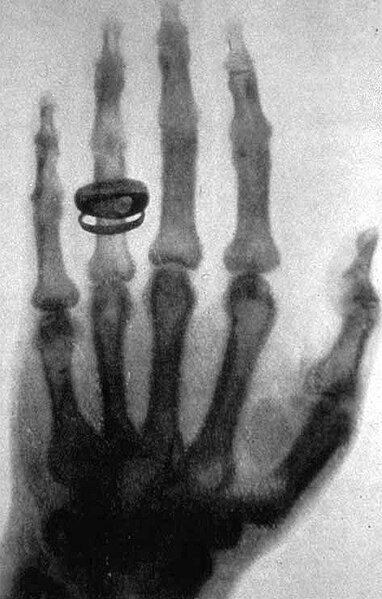

A little bit of history...